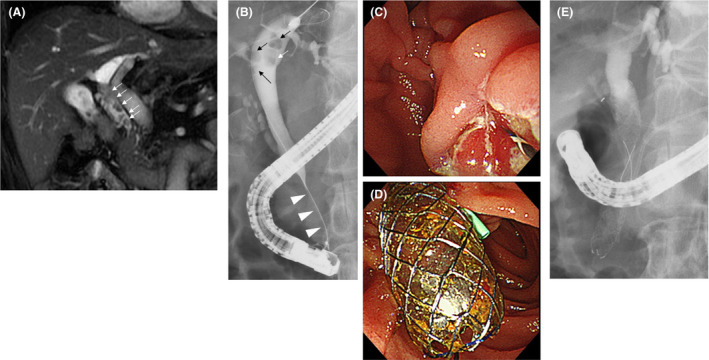

A 65‐year‐old man was admitted to our hospital for a periodic medical examination for CP. He also underwent periodic imaging examinations during follow‐up, for the last 10 years, for a benign biliary stricture caused by CP. Magnetic resonance cholangiopancreatography (MRCP) conducted as a part of these examinations revealed multiple CBD stones (Figure 1A). Contrast‐enhanced computed tomography performed 6 months before the MRCP had not revealed stones in the CBD; however, gallbladder stones were seen. It was presumed that the gallbladder stones had now progressively moved to the CBD. Therefore, we performed an endoscopic therapy for the CBD stones.

An endoscopic cholangiography revealed a stricture of the distal CBD and four CBD stones. The shortest diameter of each of the four stones (6, 5, 4, and 3 mm) was larger than the diameter of the distal CBD lumen (Figure 1B); therefore, endoscopic extraction of the stones was challenging. After endoscopic sphincterotomy (Figure 1C), we attempted to remove the CBD stones using a basket catheter, which is often used for the destruction of stones. However, the movement of the basket catheter was limited by the biliary stricture. Therefore, the basket catheter could only hold a small stone but could not extract them. The distal biliary duct was extremely narrow. Therefore, there was a possibility that the placement of multiple biliary plastic stents would be difficult, or they would not dilate the distal biliary stricture adequately to remove the CBD stones. Additionally, no pancreatic atrophy was observed during the imaging examinations. Due to the risk of injury to the pancreatic parenchyma, we did not perform dilatation with a balloon catheter. Considering all these factors, a CSEMS was placed to dilate the distal CBD stricture (Figure 1D–E). The CSEMS used in this case was BONASTENT M‐intraductal 8 mm 7 cm (Standard Sci Tech). The stent has a dumbbell shape, with an 8 mm diameter at both ends and a 6 mm diameter at the center (Figure 2). The distal tip of the stent was pushed out from the duodenum to prevent proximal migration of the stent. Due to the flared tips of the BONASTENT M‐intraductal, the risk of proximal migration of the stent is reduced. The diameter of the CSEMS (8 mm) was the same as the diameter of the CBD. The length of the distal biliary stricture was 3 cm. A 7 or 6 cm‐long stent had a midportion length of 2 cm, which is the longest BONASTENT M‐intraductal available commercially. In this case, the superior portion of the distal biliary stricture was slightly narrow. Therefore, we selected a longer stent of 7 cm. Before the CSEMS insertion, a 5‐Fr 12 cm straight pancreatic stent was placed in the main pancreatic duct to prevent postendoscopic retrograde cholangiopancreatography pancreatitis.11, 12, 13, 14, 15, 16, 17, 18, 19

Endoscopic cholangiography was repeated a week after the first cholangiography. We observed that all the CBD stones detected in the initial cholangiography had disappeared spontaneously (Figure 3A). After the CSEMS removal, the biliary sludge was removed using a balloon catheter (Figure 3B). We confirmed that there were no stones in the CBD, and the stricture of the distal CBD showed slight improvement (Figure 3C). Finally, the pancreatic stent was removed.